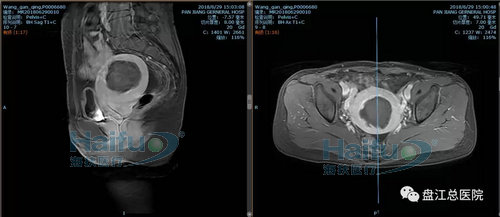

我院病例2:患者王XX,46岁,子宫腺肌症患者。

因“发现盆腔包块10+年,继发性痛经2+年”入院。于2018年6月28日行高强度聚焦超声消融治疗(HIFU)。

治疗经过:给予镇静镇痛药物后开始辐,患者诉稍有骶尾部及治疗区胀痛不适,余未诉有不适,安静休息配合治疗。总治疗时间25min。

术前磁共振增强横断位及矢状位,见病灶内明显强化

术后磁共振增强,见病灶内无明显强化,病灶发生凝固性坏死